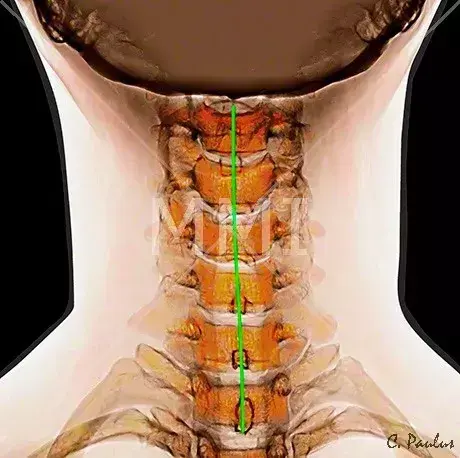

图1、正常的颈椎正位片

图2、正常的颈椎侧位片